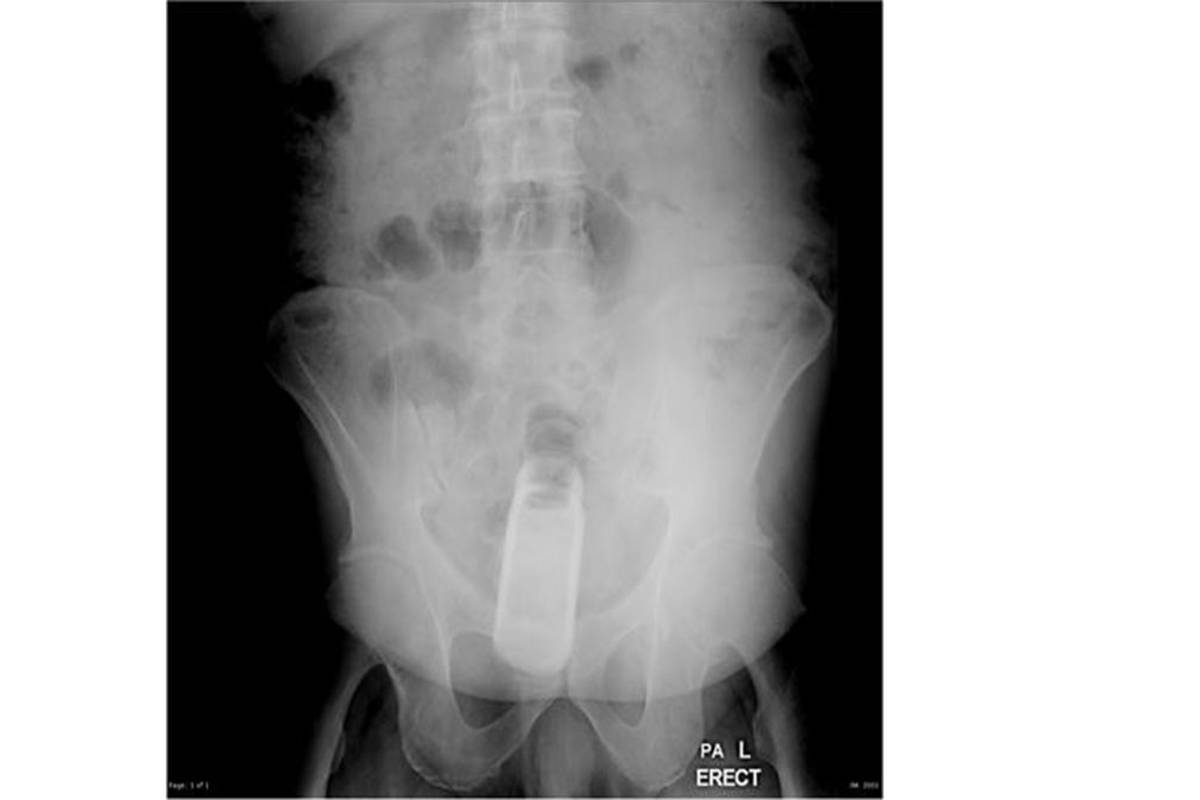

Los médicos interrogaron al paciente y luego le realizaron una radiografía que reveló que el hombre tenía un frasco en el recto, añadió.

Posteriormente, los médicos formaron un equipo de especialistas para extraerle en el quirófano el frasco que estaba dentro de un condón, precisó el portavoz del hospital.